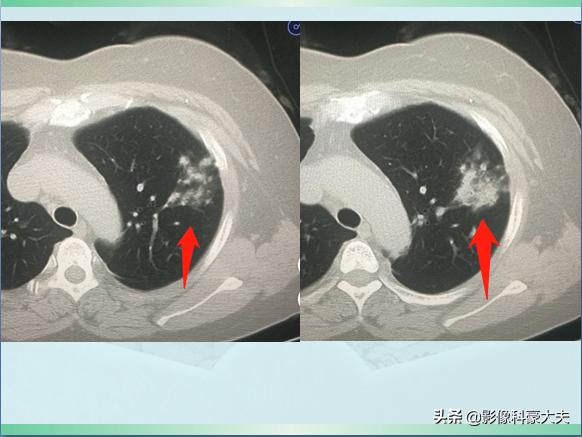

星星点点的小斑片影

上图是一位54岁女病人,因为发烧、咳嗽3天做肺部CT,发现左上肺斑片状影,密度不均,边界不清,提示肺炎。

使用抗生素治疗4天后复查,病灶密度增加,同时内部出现了几个小空洞:

融合实变,可见空洞

空洞通常是肺策划发生坏死、液化,经支气管随痰液排出后形成的,什么细菌这么厉害,会在短短4天发生坏死呢?